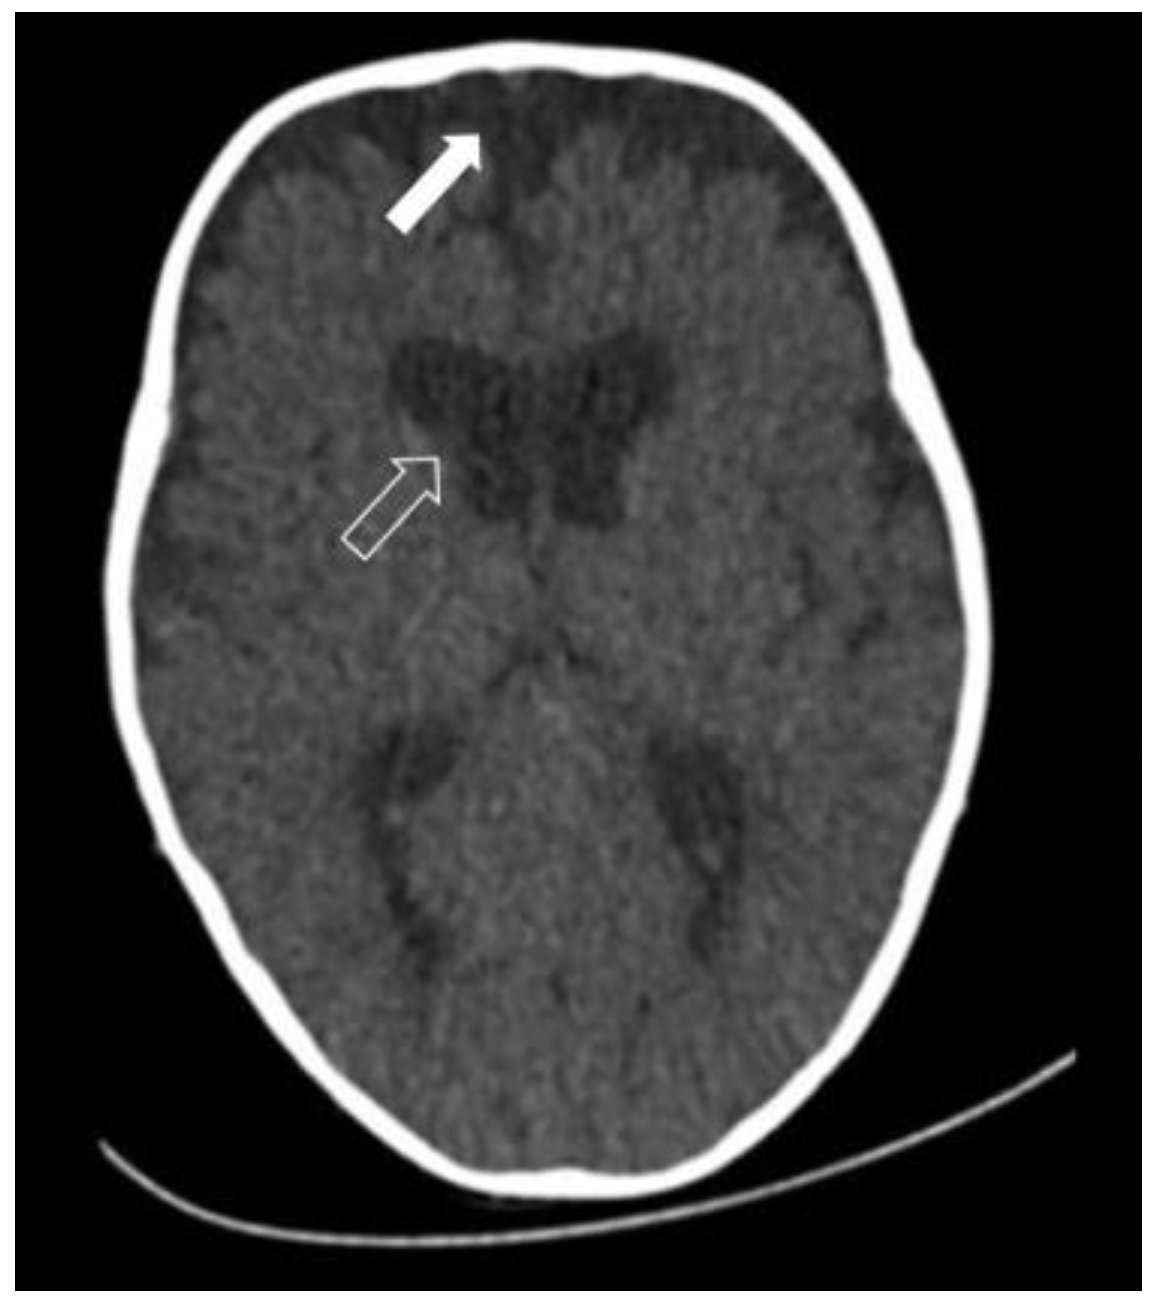

- the above-mentioned passive accumulation of CSF in the subarachnoid spaces as a result of morphological enlargement in the frontal region; and

- CSF retention as a result of a disturbance in the process of CSF resorption [14].